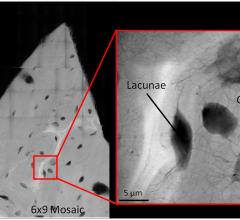

From athletes to individuals suffering from osteoporosis, bone fractures are usually the result of tiny cracks accumulating over time — invisible rivulets of damage that, when coalesced, lead to that painful break.